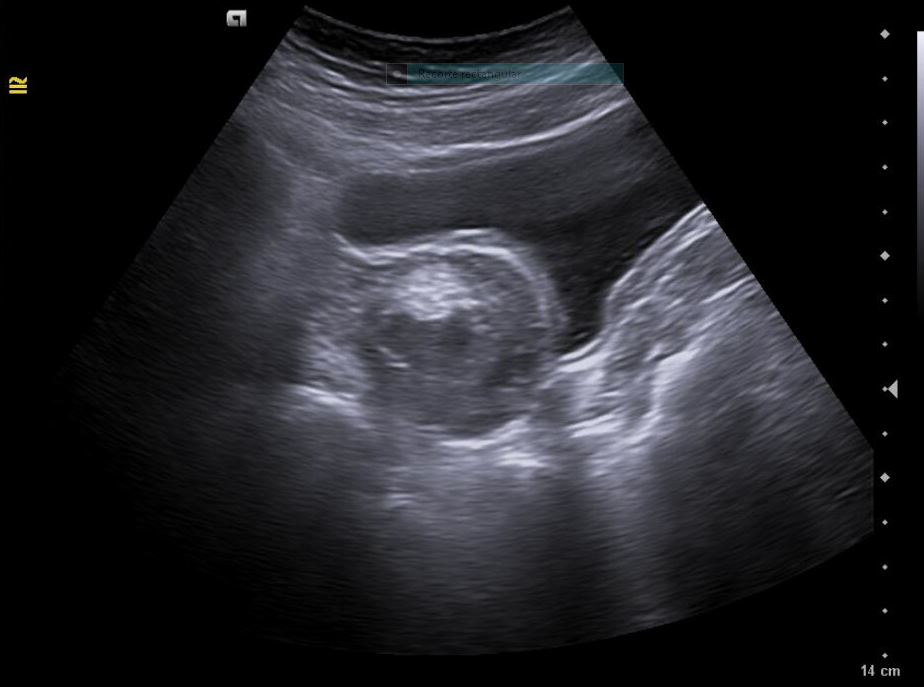

• Revisión ginecológica incidental muestra una imagen heterogénea en anexos: masa de aspecto solidoquístico en ovario derecho (43 × 33 mm), con zona hiperecoica y posible componente quístico. Se plantea teratoma como primera hipótesis diagnóstica.

Diagnóstico inicial: Teratoma ovárico derecho versus cuerpo lúteo hemorrágico.

• Formación sólidoquística en anexo derecho de 43 × 33 mm con signos sugestivos de teratoma.